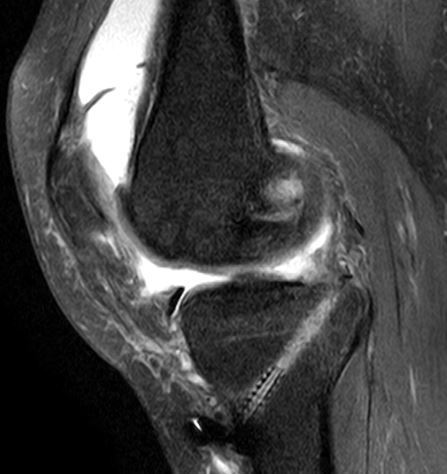

超音波検査

→膝関節の炎症が起こっていることが明確になった 水腫

水腫 血流計測 25mm/sec以上が異常